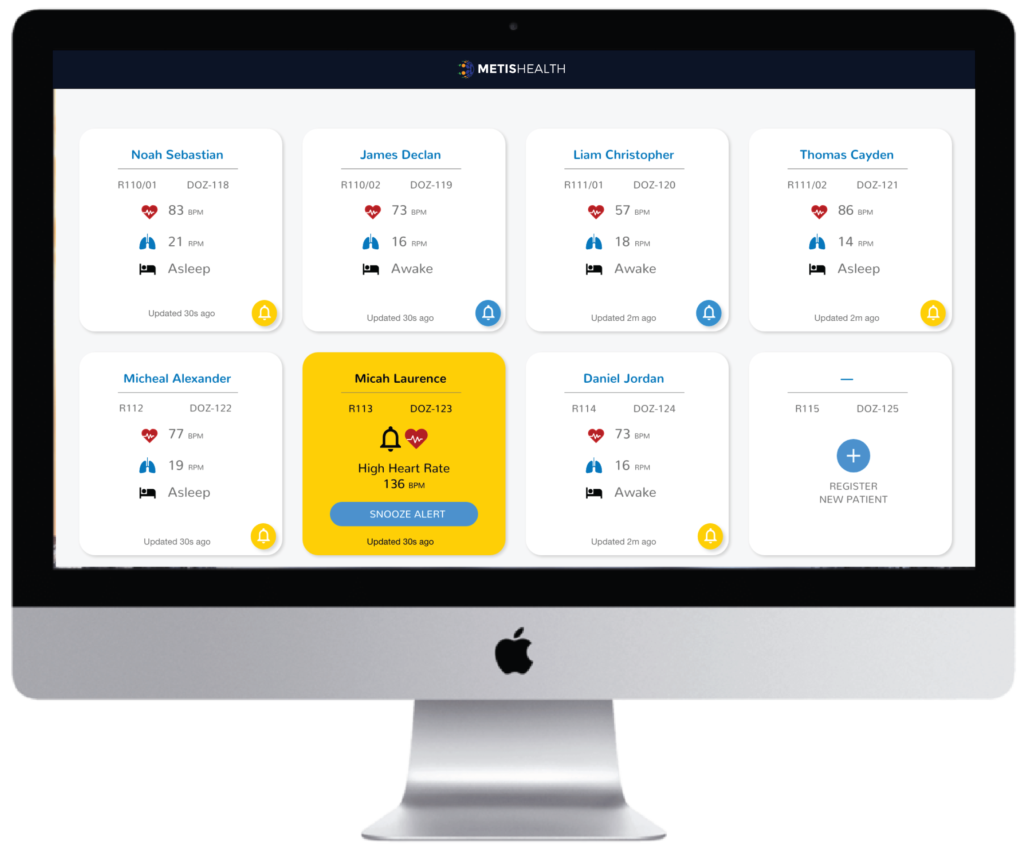

Metis Health Dozee is a contact-less, cloud connected solution to continuously monitor vitals of vulnerable patients. Our cost-effective technology provides hospitals with an efficient approach to monitor the health of the entire ward at a time. Metis Health Dozee seamlessly integrates with all hospital workflows, leveraging existing hospital infrastructure to connect healthcare providers to their patients via a web dashboard.

Easily Monitor Health of Your Entire Ward

Award winning contact free health monitoring technology that measures heart health, stress and sleep with clinical precision placed

Easy to Set-up,

Customizeable Alerts

CONTINUOUS MONITORING

DOCTORS

NURSES